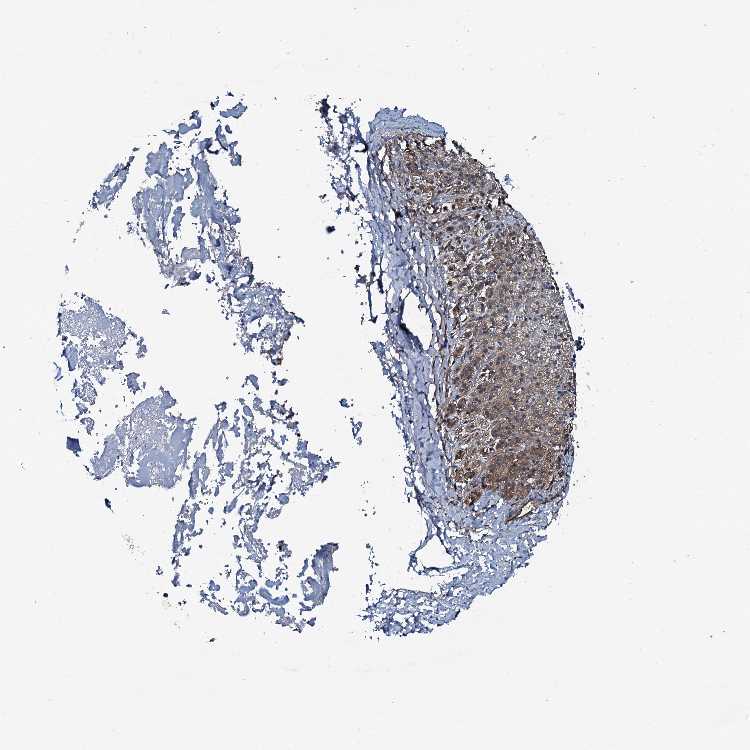

ADRENAL GLAND - Antibody stainingi

Antibody staining in the annotated cell types in the current human tissue is reported as not detected, low, medium, or high, based on conventional immunohistochemistry profiling in selected tissues. This score is based on the combination of the staining intensity and fraction of stained cells.

Each image is clickable and will lead to virtual microscopy that enables deeper exploration of all samples and also displays staining intensity scores, fraction scores and subcellular localization as well as patient and tissue information for each sample.

Antibody HPA041027

Glandular cells Low